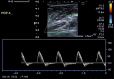

Cystic adventitial disease is a rare disorder that occurs in peripheral arteries. Calf claudication caused by compression of the popliteal artery is a typical presentation of this disease. This is a report of two cases of occluded popliteal artery decompression by percutaneous ultrasound-guided cyst aspiration. In both cases, decompression of the artery was achieved with a significant decrease in the size of adventitial cysts and restoration of flow. Both patients reported complete resolution of symptoms and no calf pain 5 years after the procedure. MR findings and resolution of symptoms in these two patients show the efficacy of percutaneous adventitial cyst aspiration in a 5-year follow-up.